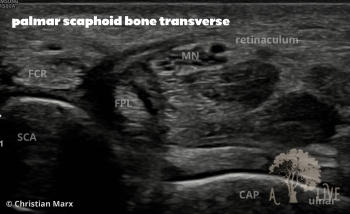

carpal ligaments